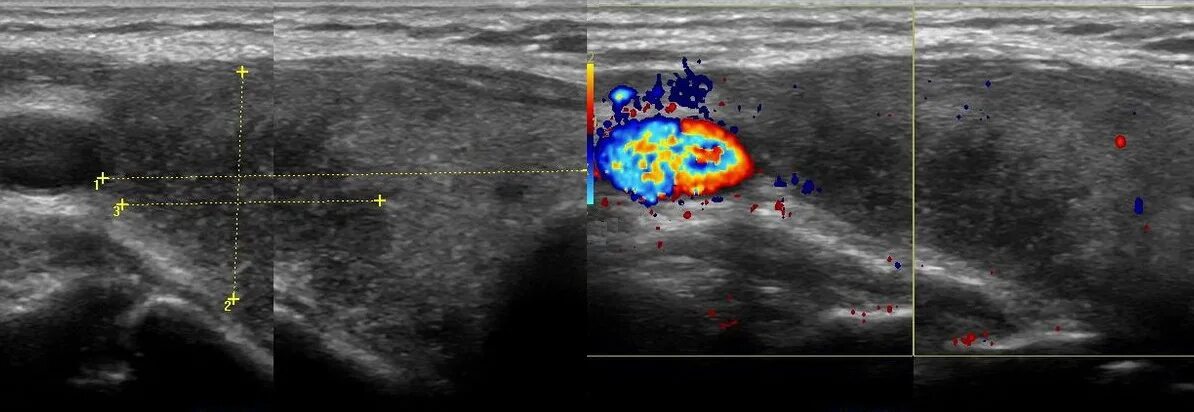

Диффузное аутоиммунное изменение щитовидной железы